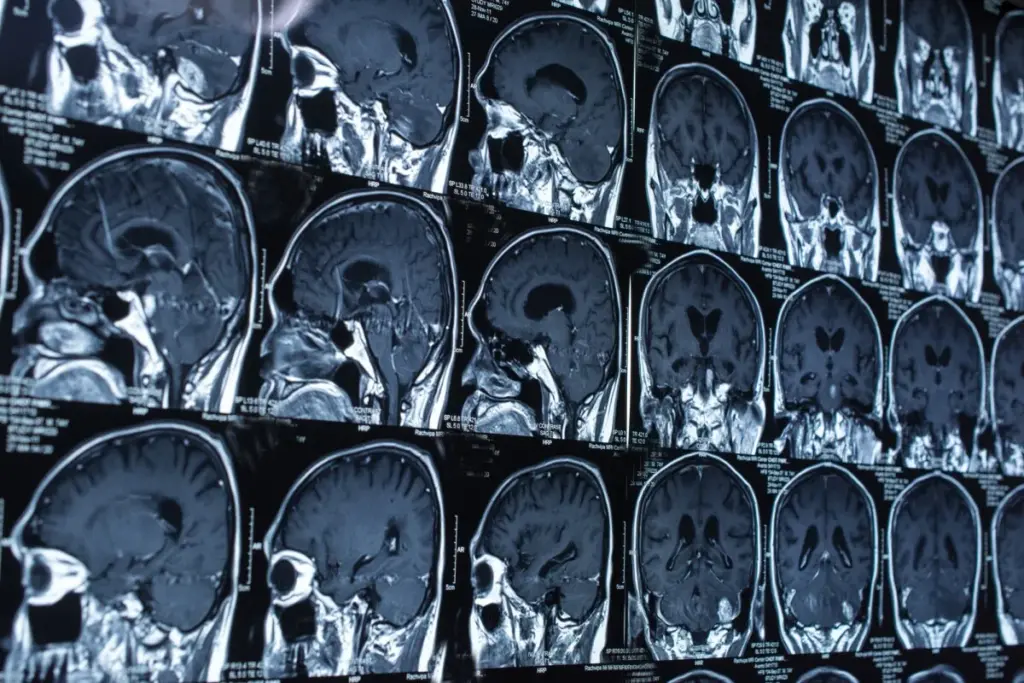

Long-term care in traumatic neurology focuses on the sequelae of repetitive injury. Chronic Traumatic Encephalopathy (CTE) is a neurodegenerative tauopathy caused by repeated head impacts (even sub-concussive ones). It leads to the accumulation of hyperphosphorylated tau protein in the sulci of the brain.

Symptoms typically appear years after the exposure ends. The early stage involves mood and behavioral dysregulation (aggression, depression, impulsivity). The later stage involves cognitive decline and dementia. Currently, definitive diagnosis is only possible at autopsy, but PET imaging for tau is an emerging diagnostic tool.